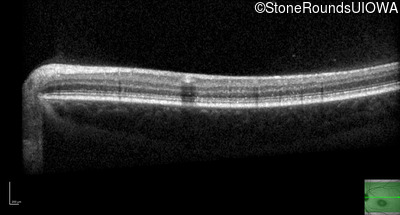

Optical Coherence Tomography - Right - 20/125 sc

Exemplar / OCT Stack

OCT Stack